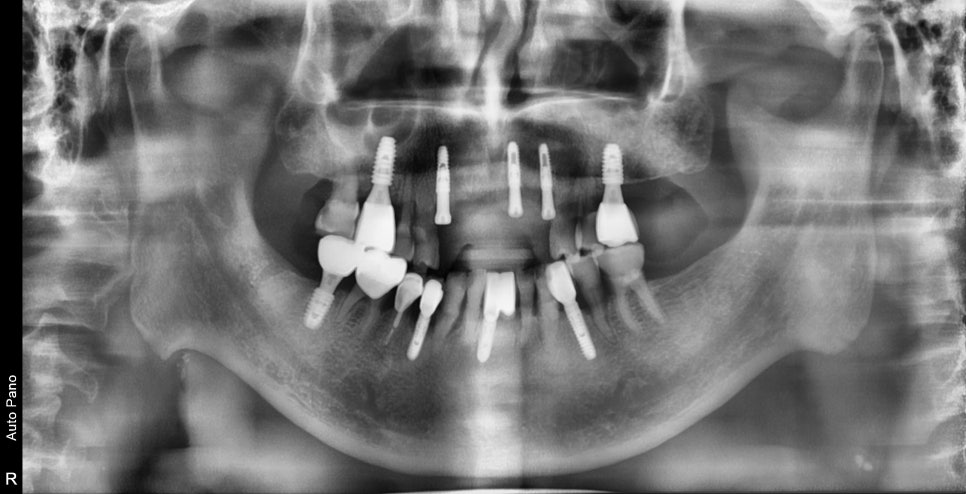

수술 후의 사진입니다.

처음 설계했던 위치에 알맞게 식립이 된 사진을 확인할 수 있습니다.

원했던 임플란트의 개수가 나오지 않아 아쉽게도 즉시 임시치아를 제작해드릴 순 없었지만

최대한 자연스럽게 제작된 임시틀니를 제작하여 일상생활에 불편감을 최소화시켜드렸습니다.

잇몸을 절개하지 않고 수술을 했기 때문에

수술 다음날에도 지혈과 통증도 거의 없을 정도로 회복세가 좋았습니다.

이제 임플란트와 함께 시행한 치조골 이식재가

고정이 되기만을 기다렸다가 보철 작업만 남았습니다.